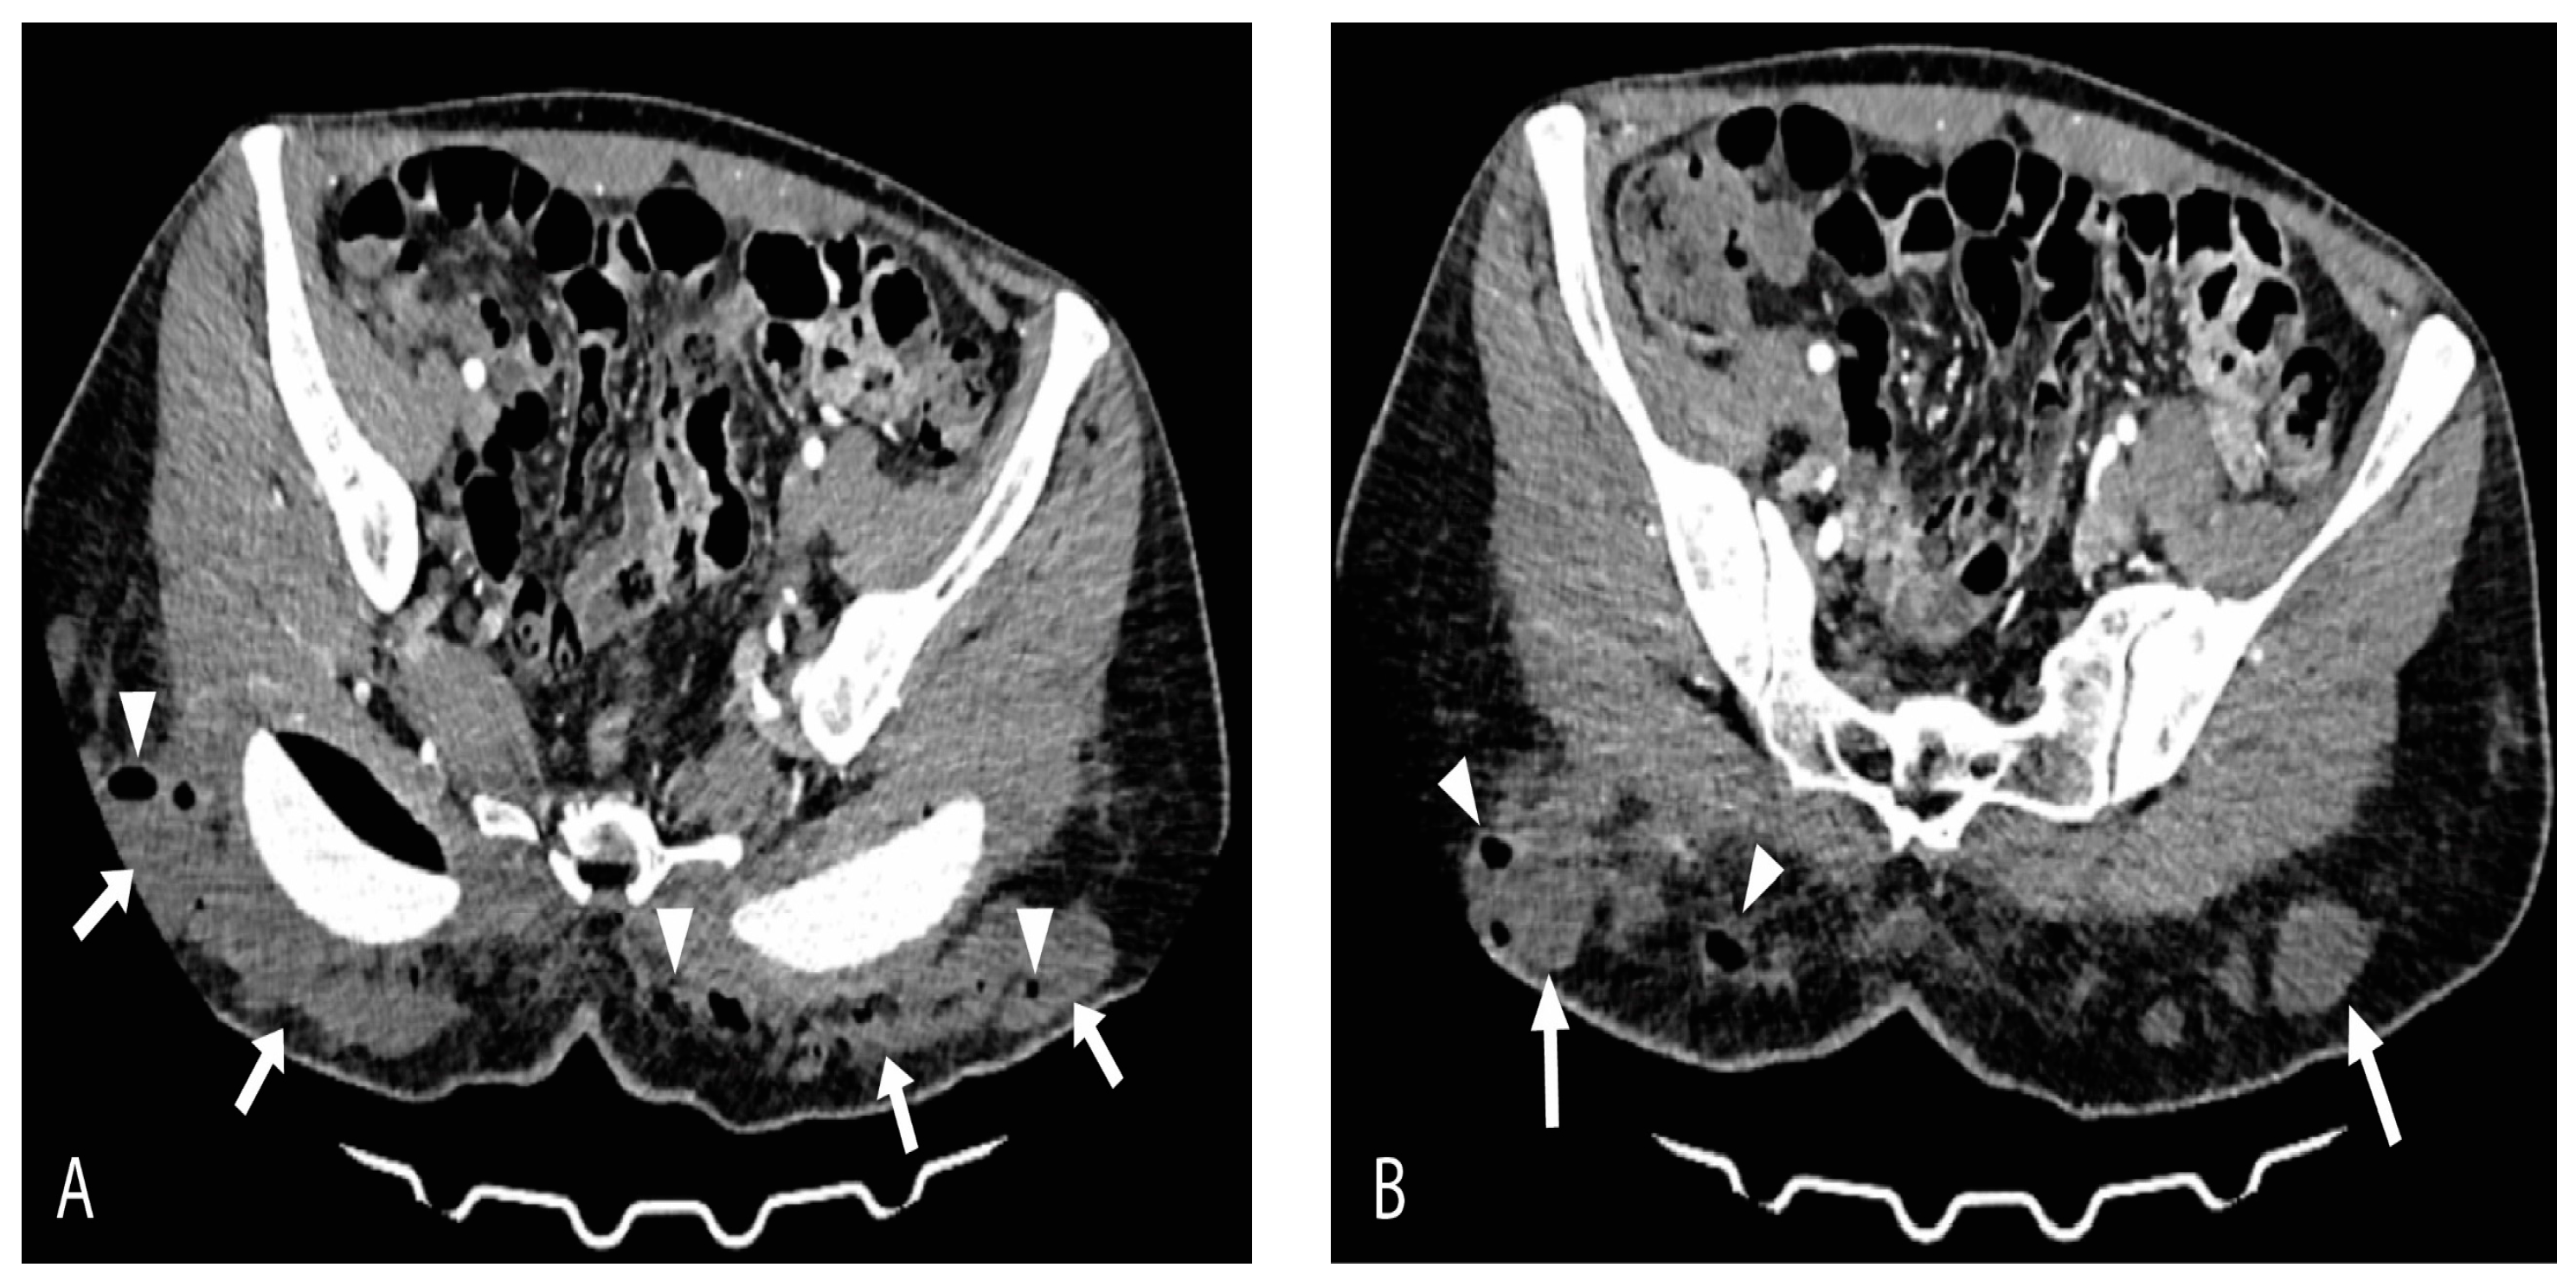

On the day of admission, the patient presented with a high fever (up to 40 °C), tachycardia, tachypnea, and dry cough. Pulse oximetry showed normal oxygen saturation with no need for supplemental oxygen. Laboratory results revealed lymphopenia (1.23 × 109/L), anemia (hemoglobin 112 g/L and red blood cells 3.57 × 1012/L), elevated fibrinogen (7.2 g/L), D-dimer (2.07 g/L), Interleukin-6 (20 pg/mL), lactate dehydrogenase (LDH 781 U/L), ferritin (387 U/L), creatine kinase (CK 212 U/L), and C-reactive protein (CRP up to 253 mg/L) while the neutrophil-to-lymphocyte ratio (NLR) was 3.9. Chest radiography showed normal findings. On physical examination, a dehisced wound with an abundant purulent secretion in the gluteal augmentation surgical site was noted as well as dusky, livid discolored gluteal skin. Additionally, palpation revealed the presence of crepitations in the gluteal region bilaterally. A computed tomography (CT) scan revealed multiple focal and confluent nonorganized fluid collections with foci of gas, fat stranding within the subcutaneous fat of the gluteal region posterior to the gluteal implants, and the posterior parts of dissected major gluteal muscles (Figure 1A,B).

Figure 1.

Axial-contrast-enhanced CT scan views (A) and (B) show massive multifocal and confluent nonorganized fluid collections (arrows) with foci of gas (arrowheads) and surrounding fat stranding within subcutaneous adipose tissue of gluteal region bilaterally. Posterior parts of dissected major gluteal muscles are also involved.

Some of the most common pathogens in SSIs reported are Staphylococcus aureus, Staphylococcus epidermidis, group A Streptococcus, and Pseudomonas aeruginosa [19,20]. Escherichia coli is the third most frequently isolated bacteria, though it is rarely a monomicrobial source of complicated necrotizing soft tissue infections [21,22]. The type of bacteria to colonize the wound mostly depends on the surgical site localization. Surgical incisions in proximity to the intestinal tract or female genitalia are more likely to have a mixed gram-positive and gram-negative flora with both facultative and anaerobic bacteria, usually responsible for complicated, purulent NSTIs. Management of SSIs is outlined in great detail in a guideline by Stevens et al. that notes that improper and untimely management can evolve into complicated, necrotizing skin and soft tissue infection. These infections are especially found to be related to surgical and immunocompromised patients, such as patients with autoimmune diseases or patients receiving immunomodulatory therapy [22]. CT findings of bilateral fluid collections filled with gas in subcutaneous adipose tissue, along with fat stranding and involvement of gluteus major muscles, with a rapid progression of systemic symptoms in our patient, presented a worrisome sign of a rather complicated infection. Given the anatomical region, the suspicion of polymicrobial necrotizing fasciitis was high, and the patient’s swab samples and pus samples were tested for aerobes and anaerobes. A fairly rare result of monomicrobial Escherichia coli necrotizing infection was obtained, given the anaerobe cultures were negative. Though not as common, various reports of virulent forms of Escherichia coli spp. as a single cause of complicated NSTI, such as necrotizing fasciitis, have been emerging in the literature. In most reports, these infections seem to be related to the immunocompetence of the patients rather than to the virulence of the bacteria [23,24].